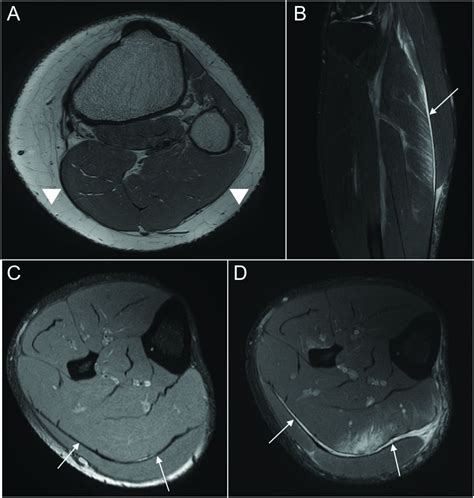

If you suspect a tear in calf, it is essential to seek medical attention for a proper diagnosis. A healthcare professional may use the following methods to assess the injury:

• Physical Examination: The doctor will examine the affected area, checking for swelling, tenderness, and range of motion.

• Imaging Tests: X-rays, MRI, or ultrasound may be ordered to visualize the extent of the tear and rule out other potential issues.